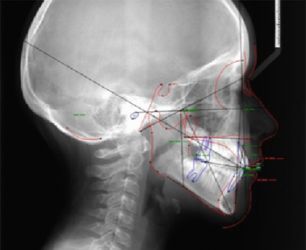

Ce dossier orthodontique est constitué de radiographies réalisées au cabinet, de moulages des dents, de photographies.

Téléradiographie de profil